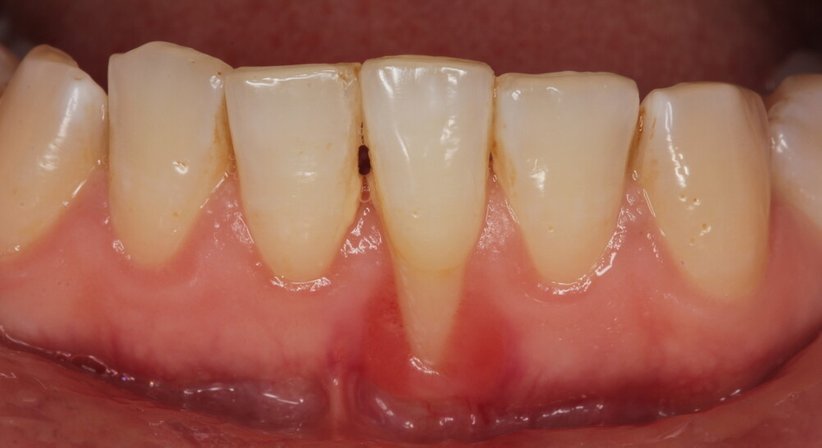

Eine Parodontitis (Parodontose) wird durch Bakterienansammlungen in Form von Zahnbelägen ausgelöst. Dabei können einfache Zahnfleischentzündungen auf das umliegende Gewebe übergreifen und auch eine Entzündung des Zahnfleisches (Gingivitis) verursachen. Bleiben die Entzündungen unbehandelt, bildet sich das Zahnfleisch zurück, Zähne können sich lockern und ausfallen. Die Erkrankung kann auch zur Gefahr für den ganzen Körper werden, da sich die Entzündung ausbreiten kann.

Eine Parodontitisbehandlung ist bei rechtzeitiger Diagnose in der Regel ohne chirurgischen Eingriff möglich. Stattdessen werden die Zahnfleischtaschen mittels spezieller Instrumente gründlich gereinigt. Die Behandlung verursacht in der Regel nur geringe Schmerzen, da sie auch unter lokaler Betäubung durchgeführt werden kann. Um die Erkrankung auf Dauer zu verbessern, ist eine regelmäßig durchgeführte Parodontitis-Nachsorge bei einer Parodontose-Behandlung Pflicht: Parodontose muss ein Leben lang beobachtet und behandelt werden.

Ist der Abbau des Gewebes bereits sehr weit fortgeschritten, kann es nötig werden, parodontalchirurgische Eingriffe vorzunehmen. Die Verfahren umfassen die chirurgische Entfernung bakteriell befallener Gewebe, Zahnentfernungen, chirurgische Wurzelbehandlungen, Zahnfleischkorrekturen, Bindegewebstransplantate oder Knochenaufbauverfahren. Wir informiere Sie gerne über Ihre individuellen Risikofaktoren als auch mögliche Therapieoptionen und führen diese auch in unserer Praxis durch.